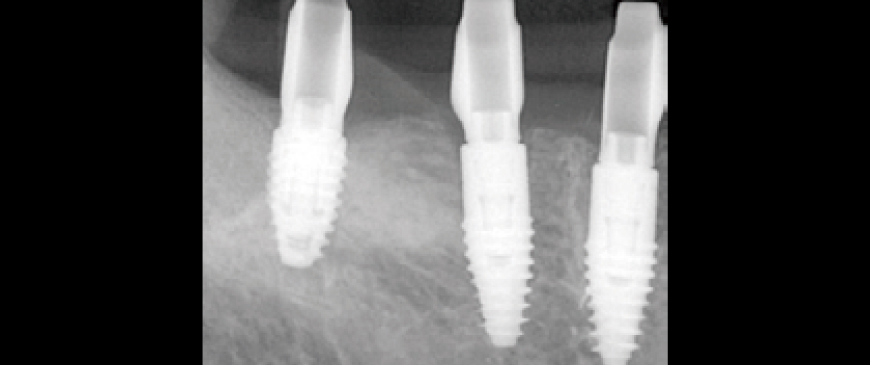

Fig 9

After approximately eight weeks, scanning was performed for impression-taking, followed by the placement of a customized abutment based on the BOPT (Biologically Oriented Preparation Technique) concept and a PMMA provisional bridge.

Fig 10

The provisional restoration was used for about three weeks, after which the final prosthesis was delivered.